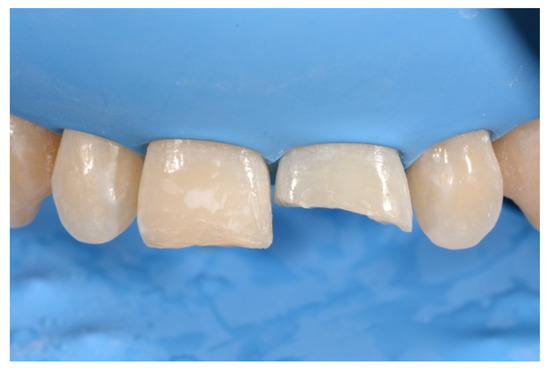

2. Case Presentation

- Molding palatal wall and incisal margin;

- Building interproximal walls with matrices;

- Layering free-hand buccal surface.